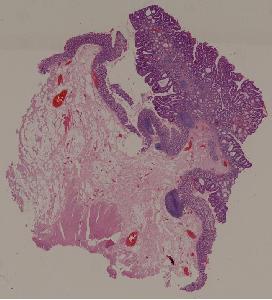

28. Adenoma of the colon